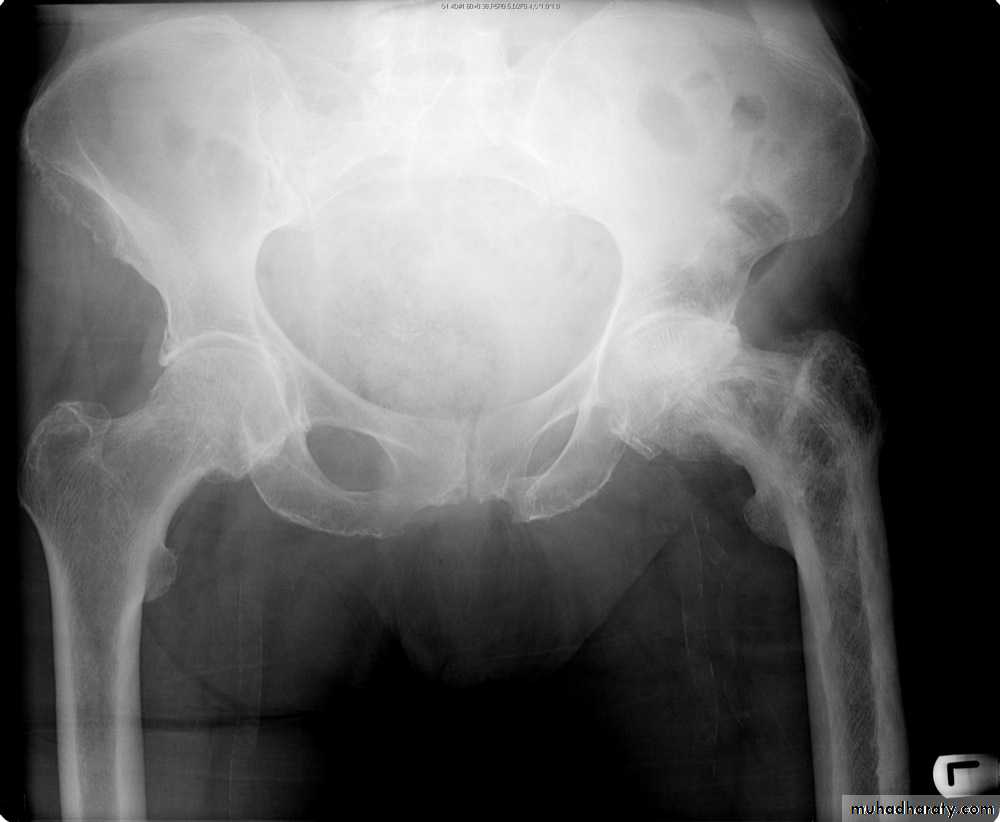

IV. computed tomography in bone disease (CT scan ) :

1.Demonestrating abnormality in the pelvis and spine2.Demonstrating the extent & characterization of bone tumour in selected cases to complement MRI